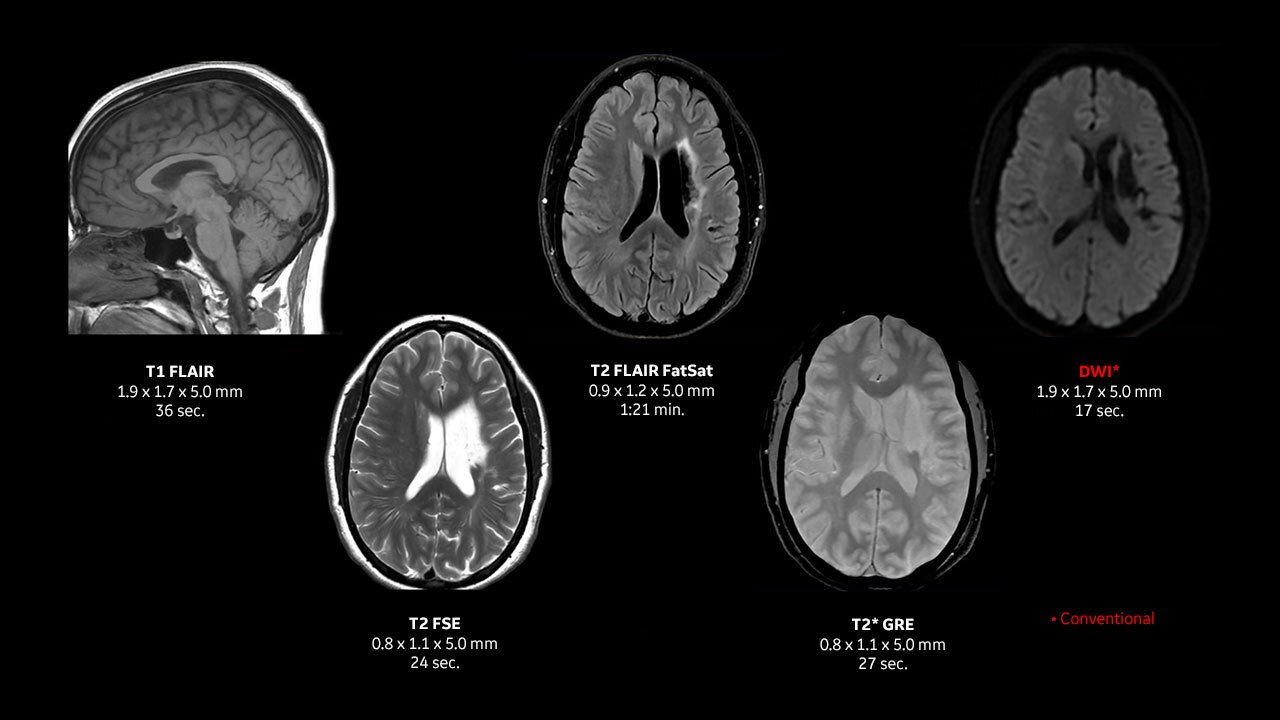

• cSound Imageformer:

全視野・全深度、画像内の全ピクセルに フォーカス処理を

行い高画質を生成